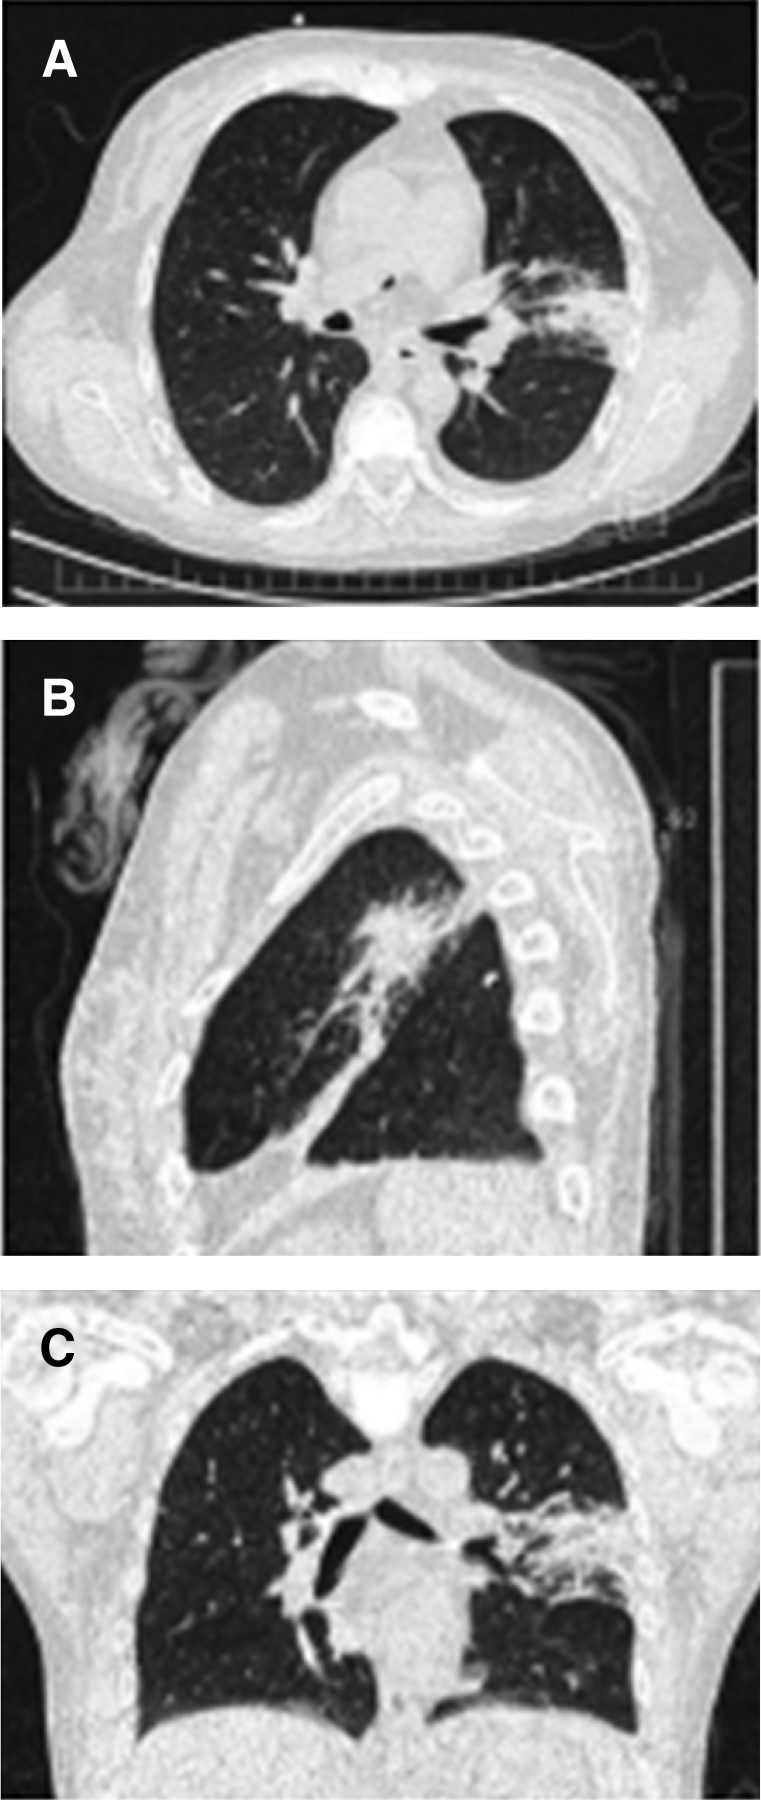

Mujer de 29 años con trasplante renal de donador fallecido en 2017. Con riesgo alto para CMV. Se dio inducción con basiliximab. Sin manejo profiláctico con valganciclovir. Inmunosupresión con micofenolato de mofetilo, prednisona y tacrolimus. Tres meses después ingresa por encontrar en consulta externa lesiones ulceradas en mejillas, además de carga viral de un millón de copias, por lo cual decide hospitalizarse. Documentándose además disfunción aguda de injerto, trombocitopenia de 95,000 plaquetas por µL, niveles de tacrolimus de 18 ng/mL. Se inicia manejo con valganciclovir y a las 48 horas presenta fiebre de 38 °C, tos seca, disnea, polipnea, motivo por el cual se solicita tomografía axial computarizada (TAC) de tórax que muestra imagen en vidrio despulido bilateral, engrosamiento pleural, zonas de atelectasia, lesión intercisural izquierda, de bordes deshilachados, aspecto de "lesión en erizo", imagen que sugiere aspergilosis pulmonar, (Figura 1) por lo cual se inicia manejo con voriconazol y al egreso virando a itraconazol. Se realiza fibrobroncoscopia y se reporta prueba de galactomanano positivo. Se mantuvo con manejo con valganciclovir por tres meses con posterior carga viral no detectada, así como itraconazol por un año con mejoría radiográfica y clínica y controles periódicos (Figura 2).

Figura 2